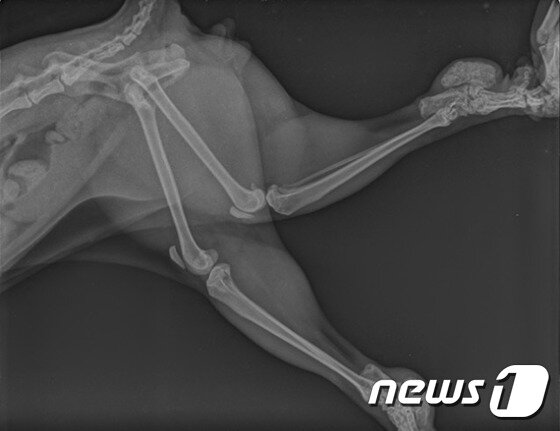

본문 이미지 - '골연골이형성증'을 앓고 있는 스코티쉬폴드 고양이의 엑스레이 사진.ⓒ News1

'골연골이형성증'을 앓고 있는 스코티쉬폴드 고양이의 엑스레이 사진.ⓒ News1